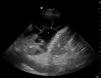

Varón de 78 años, ingresado en nuestra UCI por neumonía neumocócica. La radiografía de tórax mostraba infiltrados alvéolo-intersticiales bilaterales con derrame pleural izquierdo (fig. 1). Una toracocentesis diagnóstica, con técnica ciega, mostró líquido pleural levemente hemático, con glucosa 162mg/dl, proteínas 2,96g/dl, lactato-deshidrogenasa 366UI/l, pH7,38 y leucocitos 480μl (polinucleares 70%). Los criterios radiológicos y citoquímicos orientaban hacia un exudado no complicado, que no indicaría drenaje torácico. Se decidió realizar una ecografía torácica (fig. 2), que mostró colección pleural (*) compartimentada (flechas) y con diversas ecogenicidades, compatibles ecográficamente tanto con trasudados (anecoicas) como con exudados inflamatorios (ecogenicidad heterogénea). Además, se apreciaba atelectasia pulmonar compresiva (AP) del lóbulo inferior izquierdo, con signo de la medusa (**) producido por un fragmento del tejido pulmonar atelectasiado flotando en el líquido pleural. Se indicó una toracentesis evacuadora ecoguiada de la que se obtuvo líquido pleural amarillento, con glucosa 70mg/dl, proteínas 6,33g/dl, lactato-deshidrogenasa 968UI/l, pH7,18 y leucocitos 1.060μl (polinucleares 90%), y en la que se cultivó Streptococcus pneumoniae.

Ecografía torácica coronal en línea axilar posterior izquierda, con sonda sectorial 2-4MHz. La marca redondeada indica la localización craneal. Se observa derrame pleural (*) con signos de compartimentación (flechas) y diferentes ecogenicidades. Se aprecia atelectasia pulmonar (AP) y el «signo de la medusa» (**) descrito en el texto. D=diafragma; B=bazo.